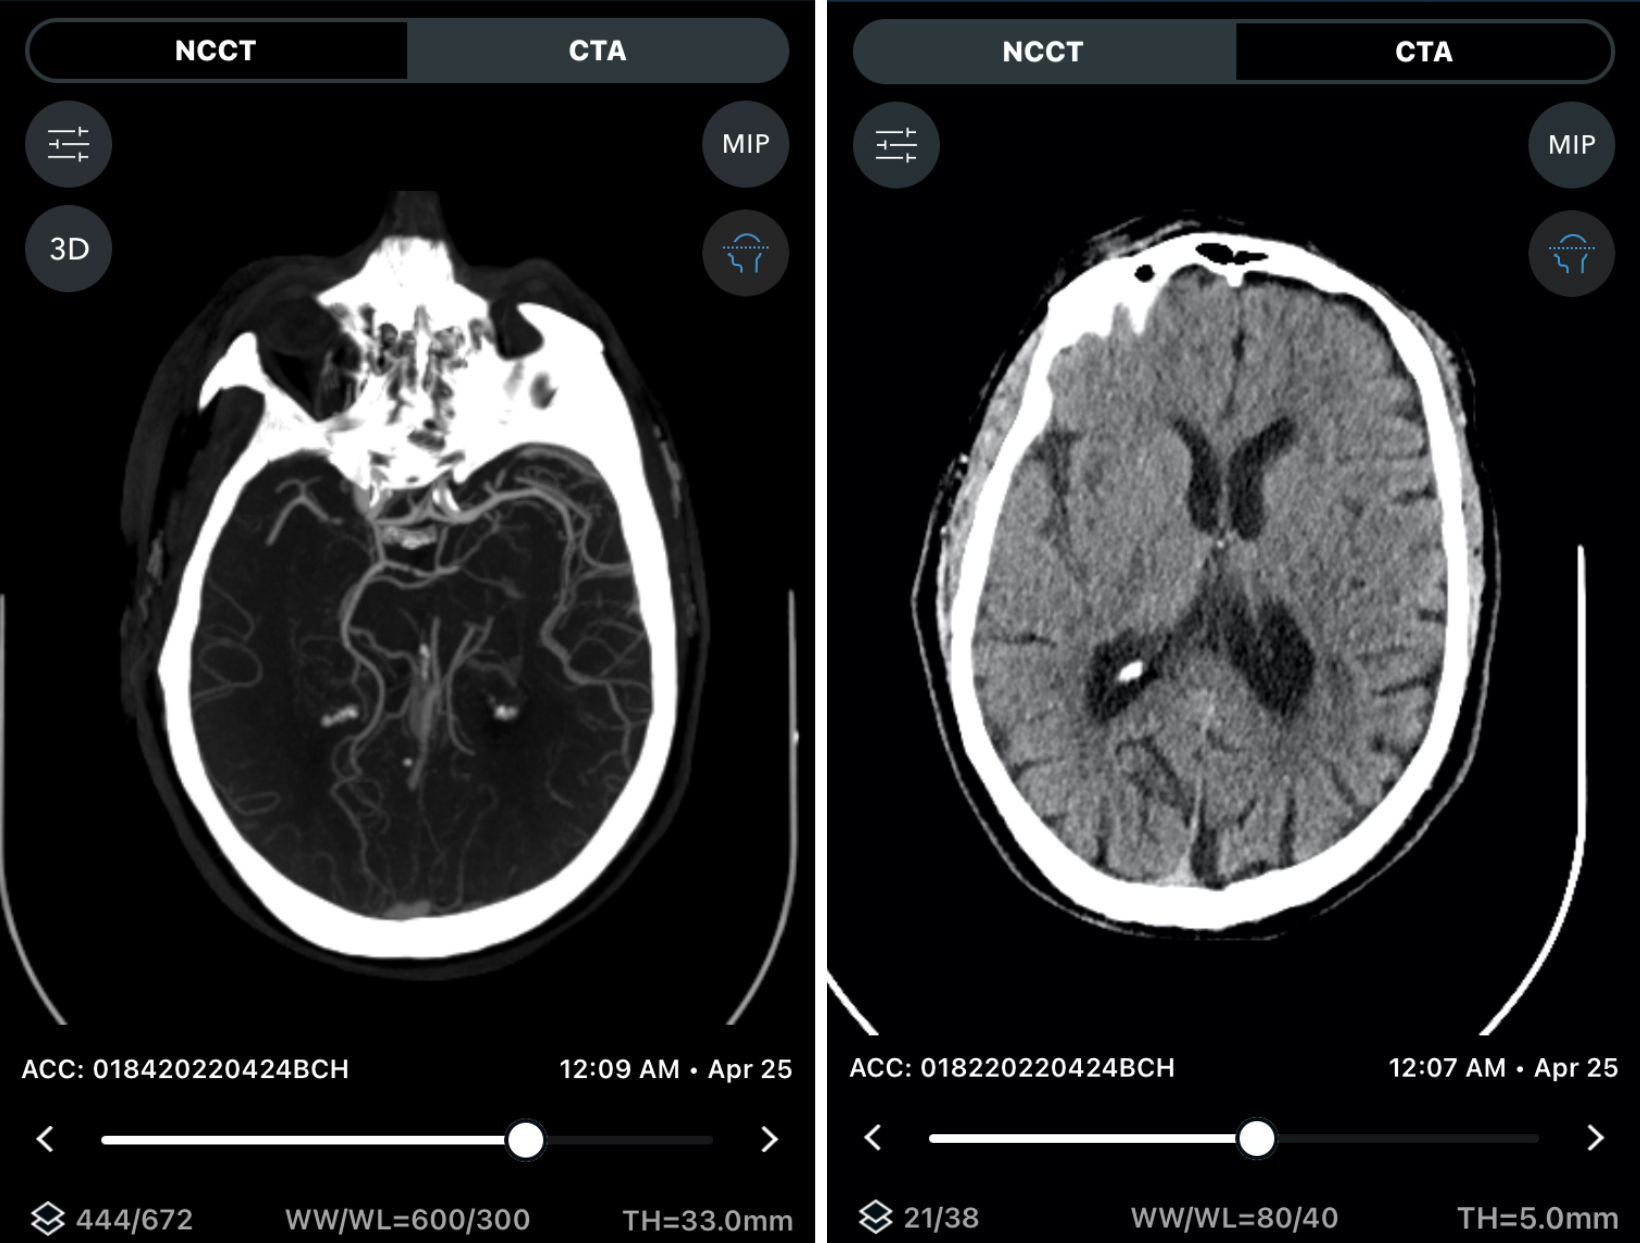

The whole concept of bringing patients DTA is predicated on good image quality so you can detect hemorrhage with reliability, and you can also detect the size of the core infarct with reliability, with high-resolution imaging. The ARTIS icono, with its cone beam CT, has reached the threshold where we’re able to identify the size of the core infarction and reliably identify hemorrhage. Now we have excellent image quality in the angio suite so we can safely bypass CT. And that’s because of the improvements in technology.

The patient was transferred to Swedish Medical Center within 60 minutes of the previous CT, which was visualized remotely with AI technology (Figure 2).

The patient was sent DTA and a Sine Spin head CT was done (Figure 3). Thrombolysis in cerebral infarction (TICI) 3 was achieved after 1 pass (Figure 4). Time from door to recanalization was 43 minutes. Figure 5 shows the patient’s MRI after 24 hours.